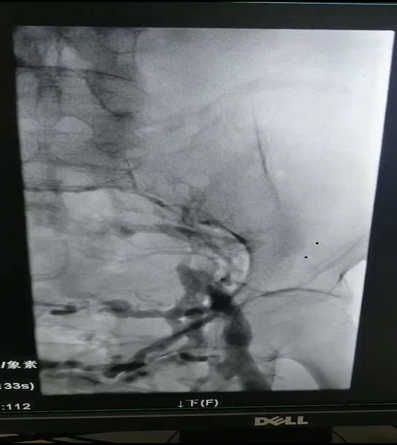

患者辛某,两月前左腿肿胀来我院就诊,B超检查发现左下肢深静脉血栓,经下腔静脉滤器植入术标准抗凝治疗后,患肢肿胀明显改善,两月后复查超声,左下肢深静脉内血栓基本消失,但左腿肿胀仍时轻时重。近期又在我院住院治疗,经左下肢顺行造影发现左侧髂静脉完全闭塞。经由交大一附院刘亚民教授会诊后,诊断为左侧髂静脉压迫综合症。

6月30日晚8时,在刘亚民教授的精心指导下,介入科李渊博主治医师与科室医护人员为该患者实施了血管开通、球囊扩张成形及支架置入术,术后造影,左侧髂静脉通畅,患者安全返回病房。